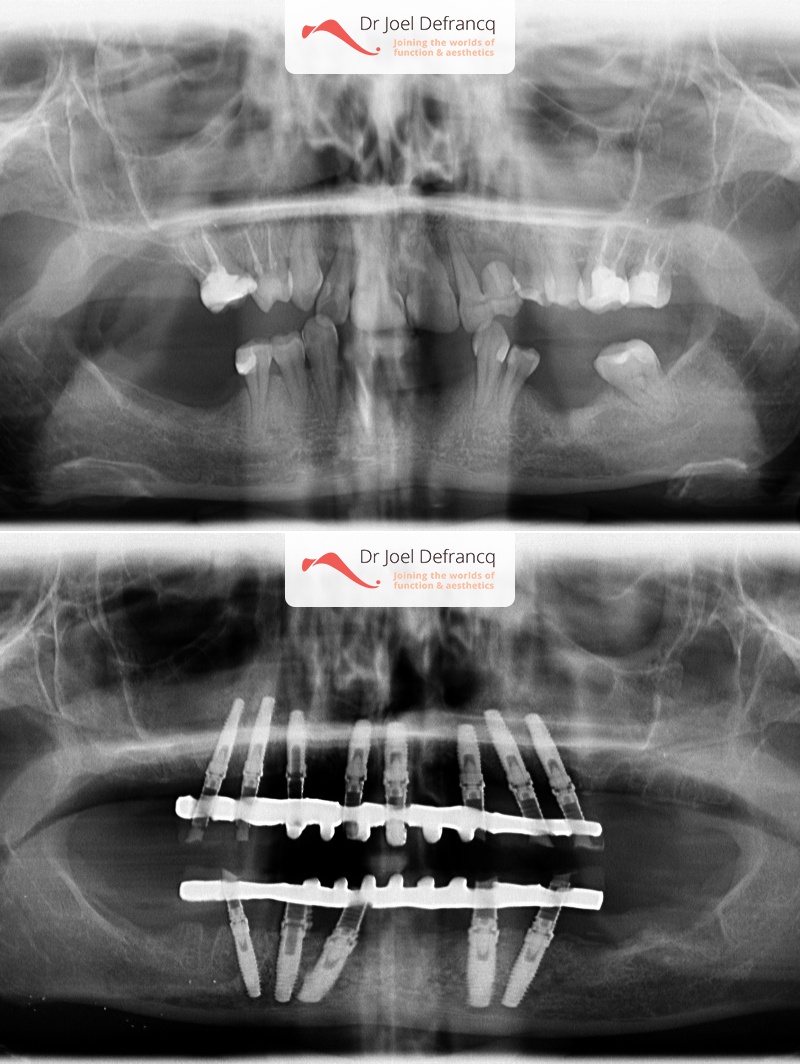

Balera: Extreme deep bite - implants

Behandeling tandheelkundige implantaten

- Vaste tanden op implantaten (bovenkaak)

- Vaste tanden op implantaten (onderkaak)

- Implantaten met beenopbouw